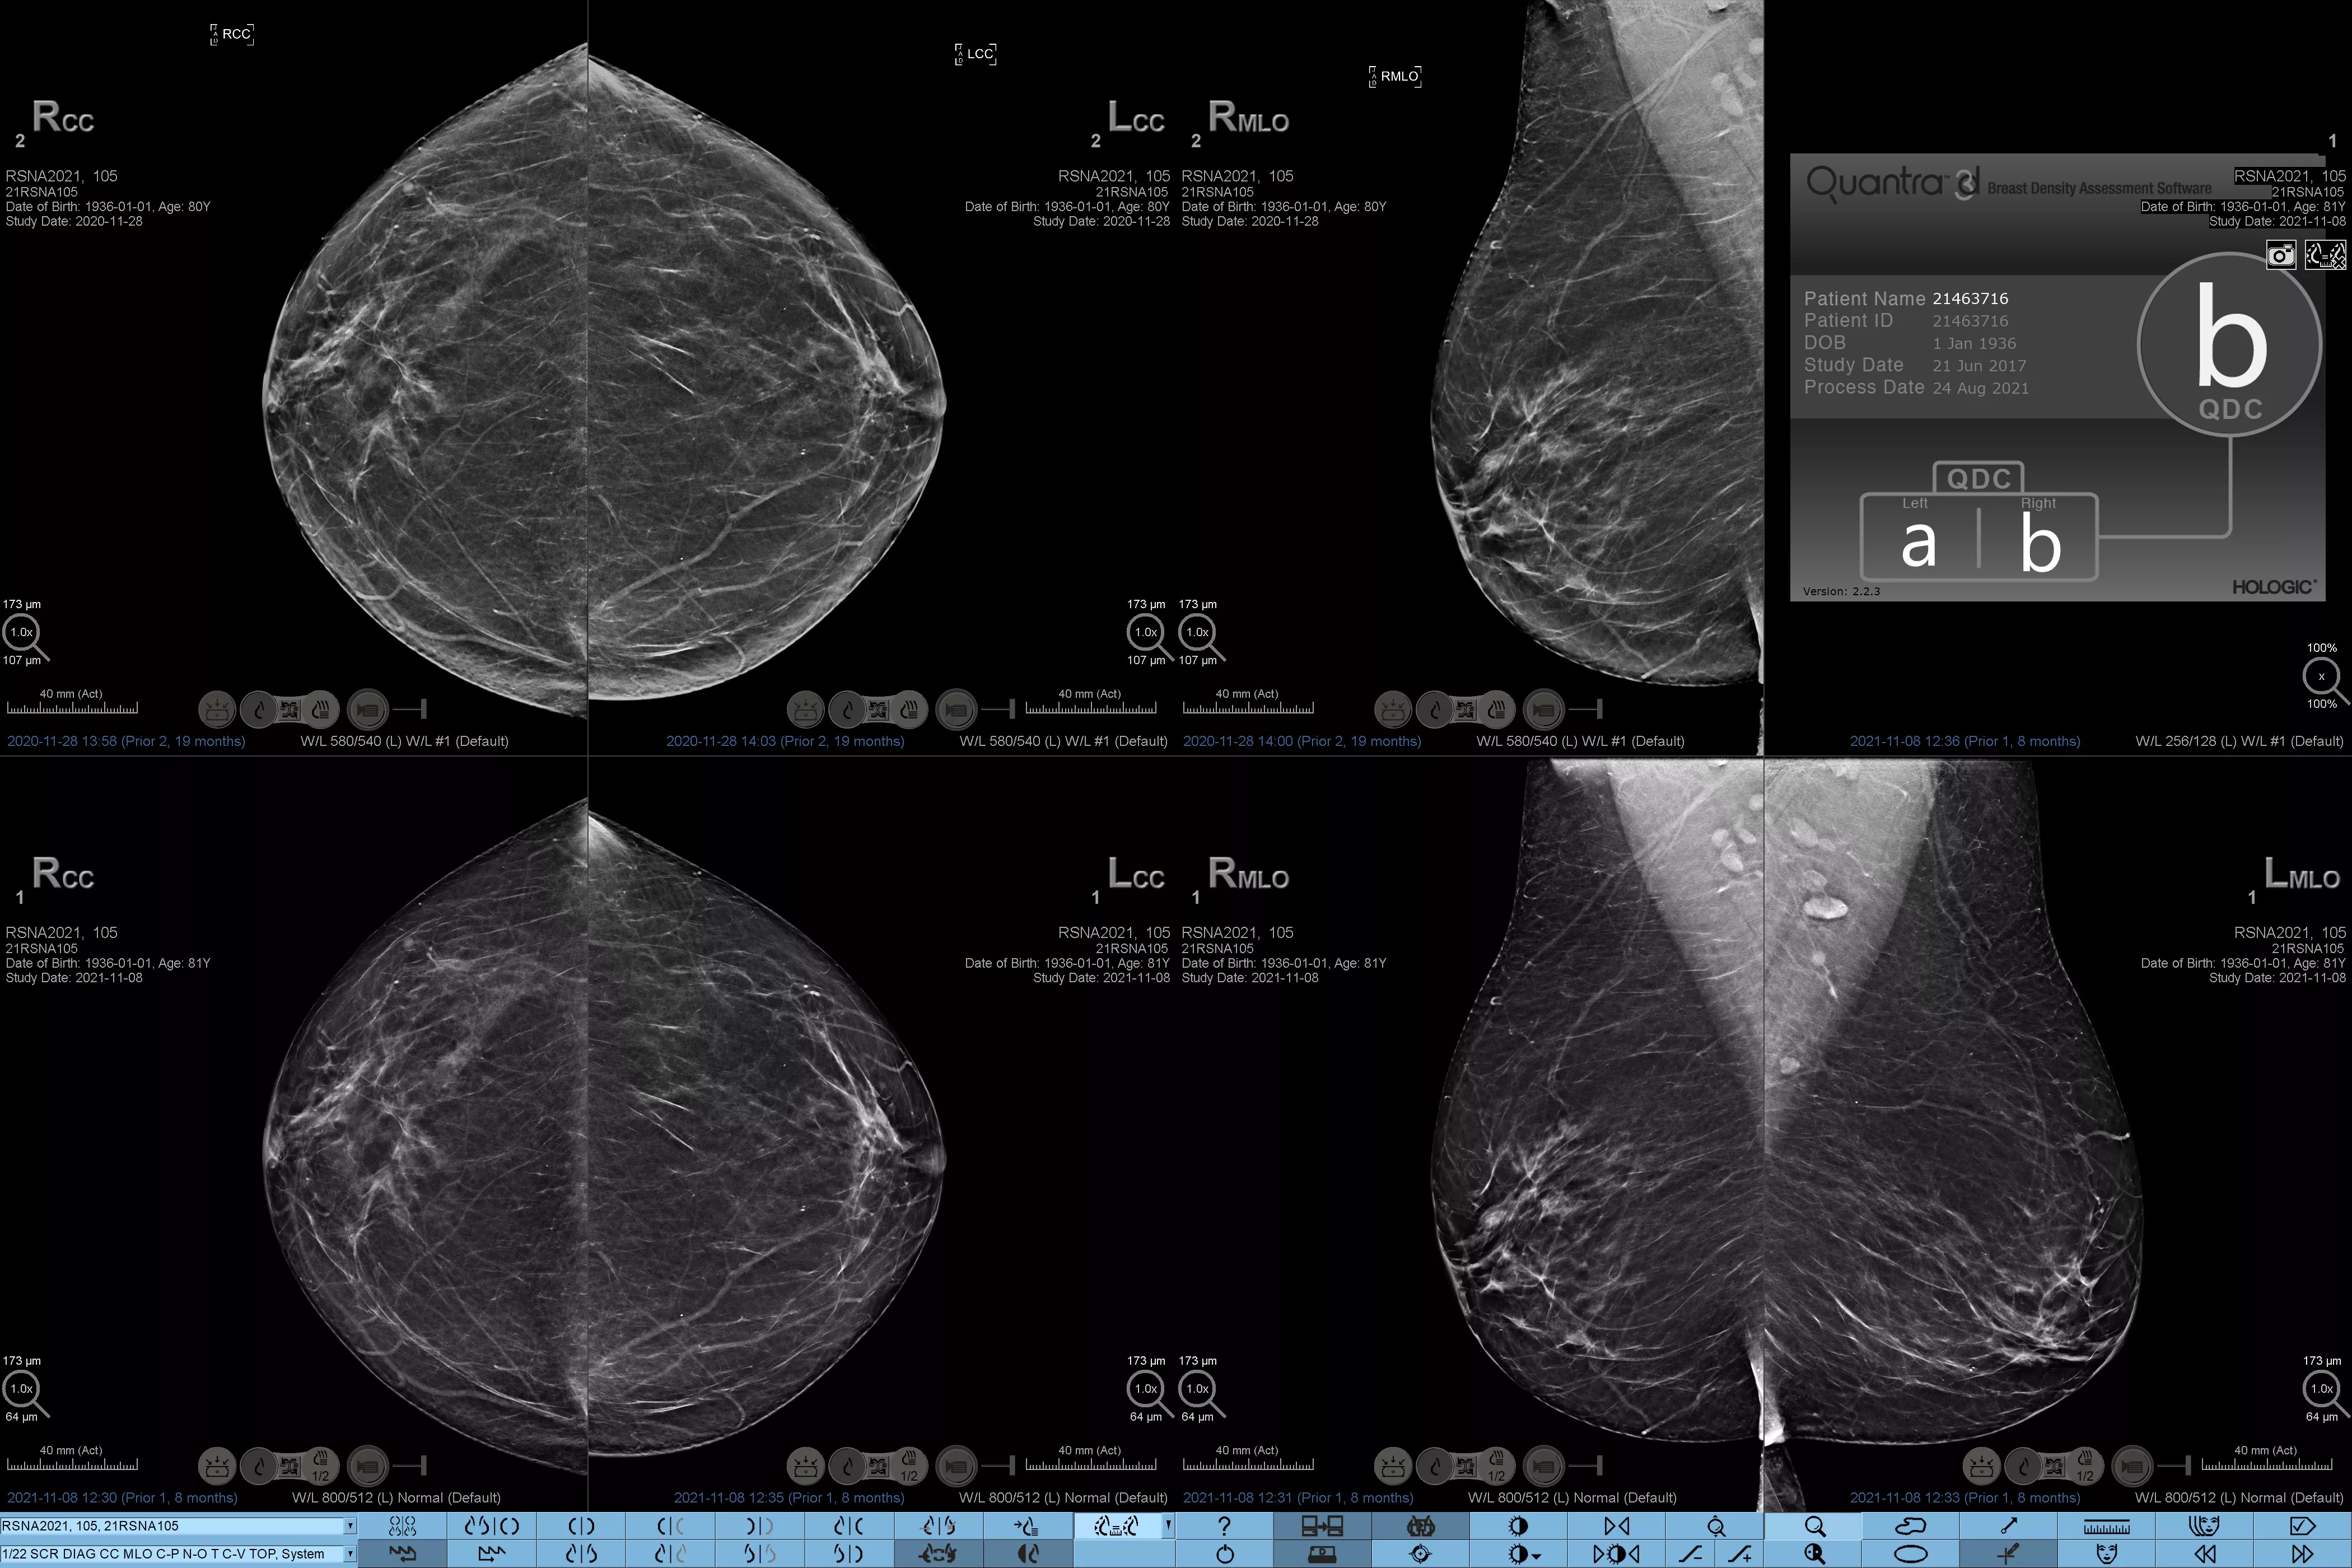

Det är känt att en hög brösttäthet ökar en kvinnas risk för bröstcancer.1 Behovet av noggrann och opartisk analys är därför kritiskt. Med hjälp av maskininlärning analyserar Quantra Technology-programvaran både 2D™- och tomosyntesbilder för fördelning och textur av parenkymal vävnad. Den kategoriserar bröst i fyra bröstkategorier utifrån sammansättning enligt riktlinje från American College of Radiology (ACR) BI-RADS Atlas 5th Edition.2

* Poängbedömningar baseras på ACR BI-RADS-kategorier enligt de reviderade riktlinjerna från American College of Radiation (ACR) BI-RADS Atlas 5th Edition. Detta motsvarar mönster och textur jämfört med volym vid bedömning av täthet.

8. Kategorier för bröstsammansättning enligt beskrivningen i ACR BI-RADS Atlas.